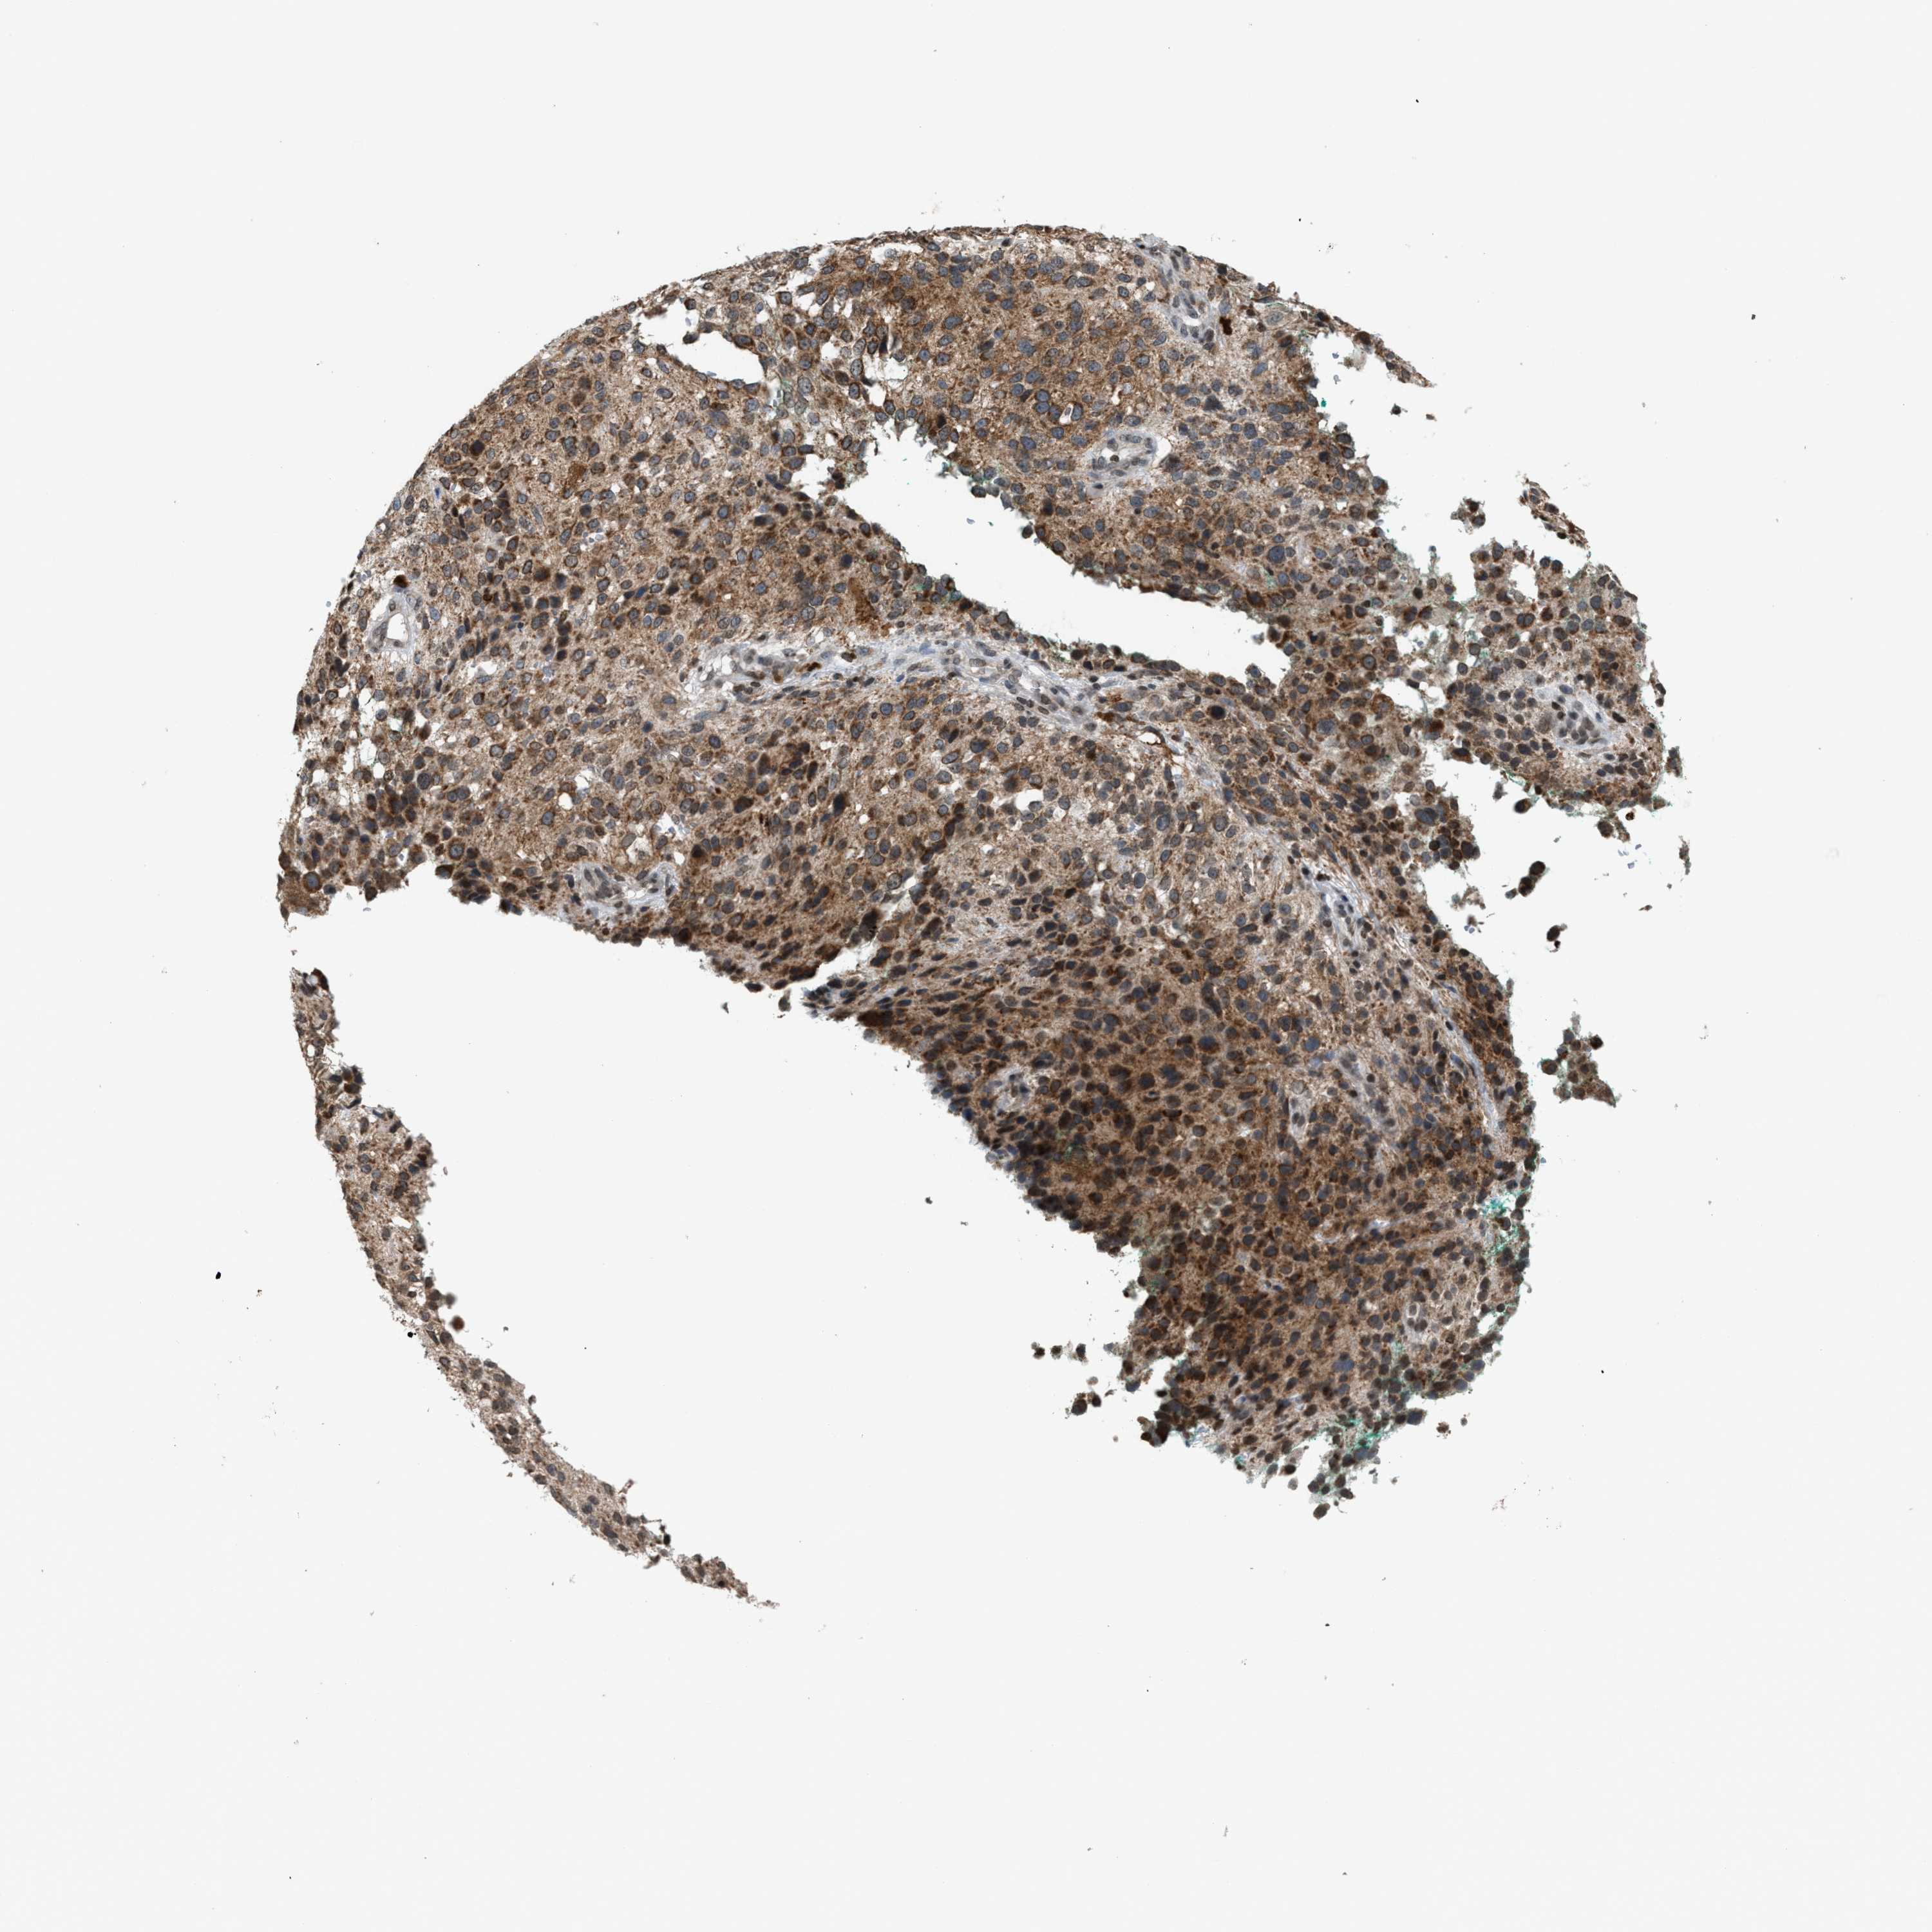

MELANOMA - Protein expressioni

A mouse-over function shows sample information and annotation data. Click on an image to view it in a full screen mode. Samples can be filtered based on level of antibody staining by selecting one or several of the following categories: high, medium, low and not detected. The assay and annotation is described here.

Note that samples used for immunohistochemistry by the Human Protein Atlas do not correspond to samples in the TCGA dataset.

Antibody stainingi

Antibody staining in the annotated cell types in the current human tissue is reported as not detected, low, medium, or high, based on conventional immunohistochemistry profiling in selected tissues. This score is based on the combination of the staining intensity and fraction of stained cells.

Each image is clickable and will lead to virtual microscopy that enables deeper exploration of all samples and also displays staining intensity scores, fraction scores and subcellular localization as well as patient and tissue information for each sample.

Antibody HPA022470

Antibody HPA031079

Staining

High

Medium

Low

Not detected

Intensity

Strong

Moderate

Weak

Negative

Quantity

>75%

75%-25%

<25%

None

Location

Nuclear

Cytoplasmic/membranous

Cytoplasmic/membranous,nuclear

Malignant melanoma, NOS

Malignant melanoma, Metastatic site